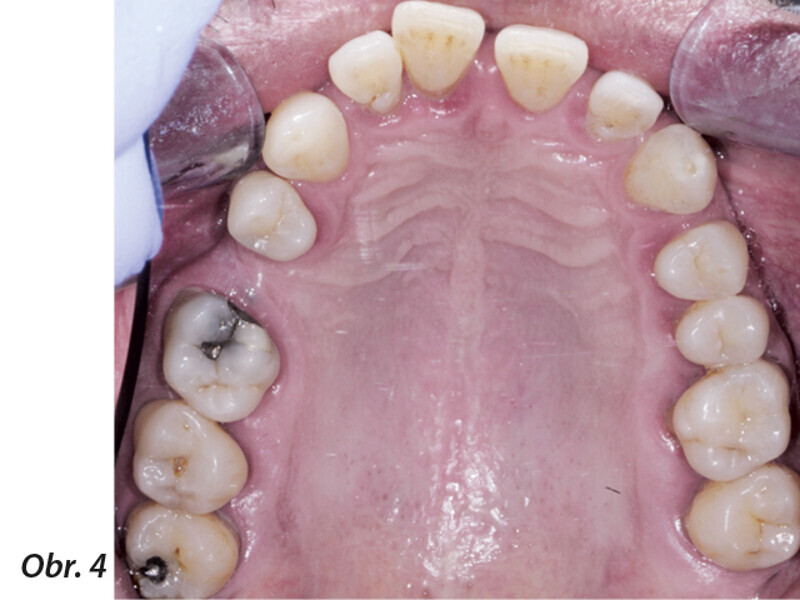

Multidisciplinární léčba u pacienta se závažnou parodontitidou